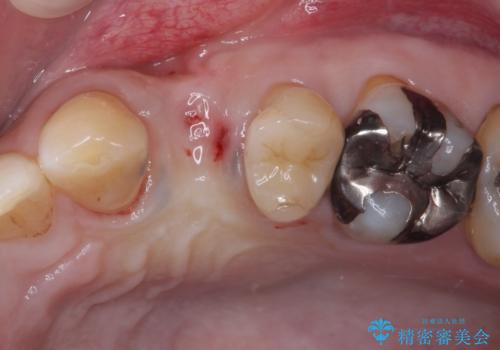

- 他院で抜歯が必要と診断され、再度診断を希望して来院された患者様です。

顕微鏡下で診察を行ったところ、歯根が垂直に破折していたため、抜糸してインプラントによる補綴治療を行うこととしました。